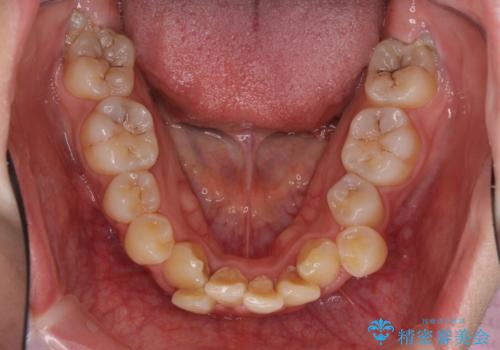

インビザラインが続けられない ワイヤー矯正での抜歯矯正 その1

- 八重歯やデコボコをインビザラインで治療したいとのことで来院された患者様です。

インビザライン単体で治療を行うには叢生が強いと判断されたため、事前にワイヤー装置で抜歯矯正を行い、ある程度改善してからインビザラインにて仕上げていくこととしました。